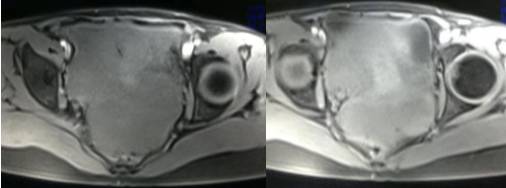

MR检查:

病理结果:黄体血肿

根据时间不同MR信号也有所不同,TIWI脂肪抑制序列可以鉴别脂肪和出血。

卵巢囊肿:呈均匀的T1WI 低信号,T2WI 高信号,边界清楚,壁薄,大多数病灶直径≤5 cm,但囊肿的起源及定性诊断困难。

卵巢囊腺瘤:呈囊性或囊实性肿块,边界清楚,壁厚,有分隔或结节( 直径≤3mm) ,浆液性囊腺瘤:囊液呈T1WI 低信号,T2WI 高信号,黏液性囊腺瘤呈T1WI 高信号、T2WI 稍高信号,T2WI 信号高于水,信号较均匀,增强扫描囊壁及壁结节强化。

畸胎瘤:多呈囊性或囊实性,单房或多房状,囊内液体可有分层,实质由多胚层策划构成,MR 信号不均,肿块内见脂肪信号有利于畸胎瘤的诊断。

巧克力囊肿:常呈多发的单囊或多囊改变,病灶大小不等,囊壁厚薄不均,囊内信号复杂,囊内或各囊腔间血液因出血时期不同,信号常呈多样性,囊肿内反复出血、破裂,形成相互粘连的多房性囊肿,是其较为特征性的表现。

在鉴别卵巢畸胎瘤、出血性囊肿或巧克力囊肿时,MR 脂肪抑制T1WI 可明确肿块内高信号成分是脂肪还是出血,同时由于脂肪策划与非脂肪策划的共振频率不同,在两者交界处沿磁场频率编码方向出现化学位移伪影,但出血性囊肿与巧克力囊肿的鉴别有时较为困难。